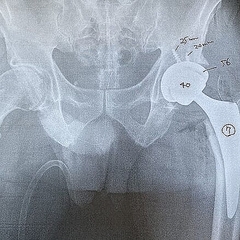

加藤氏は今年1月に左の股関節を人工股関節に換えたが、「痛みがなくなった」と言う。股関節の痛みに襲われたのは講談社を60歳で退職し、フリーランスとして活動を始めた2017年頃。友人と計画した富士登山に向けてのトレーニングがきっかけだった。

「50歳以上の患者さんで軟骨が失われた場合は、骨盤側の寛骨臼というお椀状の骨と大腿骨の両方に人工物を入れます。傷んだ関節を、金属やポリエチレンで作った人工関節に置き換えるものです。軟骨が残っていれば大腿骨を削るなどの『骨切り術』もありますが、股関節の痛みに我慢を重ねて症状が悪化したあとは、人工関節しか選択肢がなくなってしまいます」

加藤氏は1月の手術後、退院後も週1回のリハビリに通い、3月中旬に“卒業”できたという。

「今は1万歩歩いても痛みはなく、股関節はよく動いて腰も良く回ります。歩くのも苦痛だったのが、スイスイ歩けて快適で、主治医からは『もうゴルフに行ってもいい』と言われています」(加藤氏)